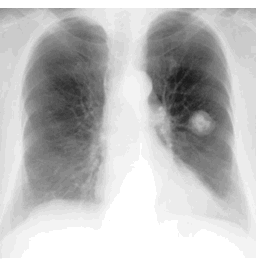

CASE 2

How would you describe the LUNG abnormality in each of these cases?

C